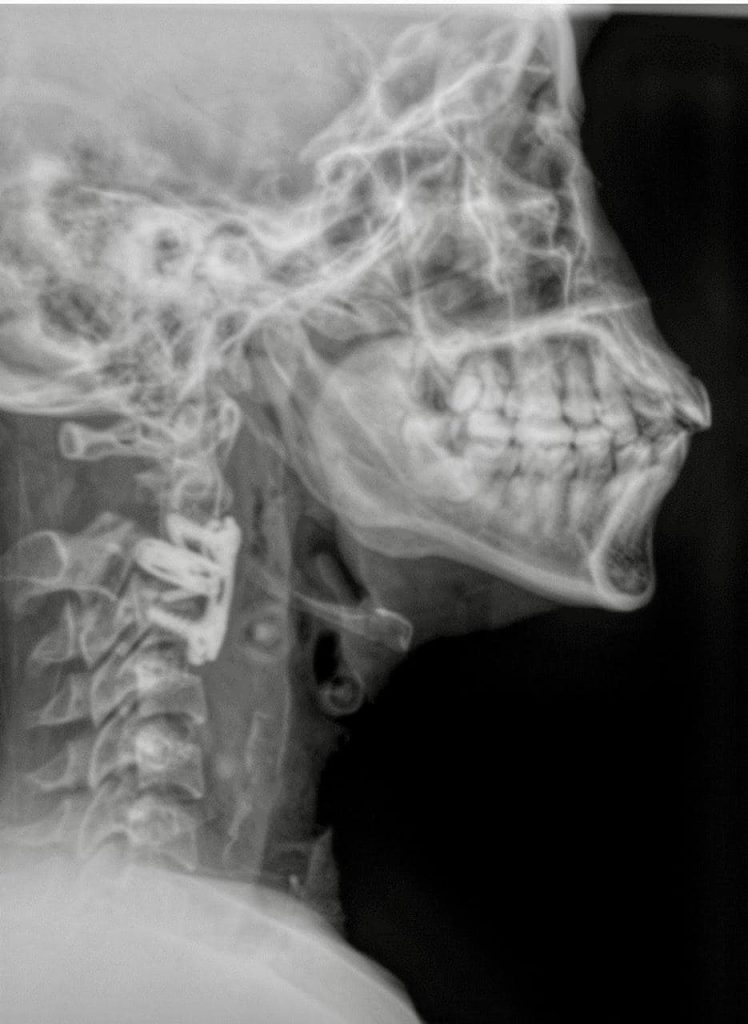

Durante la primera cirugía le colocaron un halo cefálico en el cráneo, que permitió dar tracción a la vértebra luxada y acomodarla nuevamente en su lugar, dos días después se realizó un segundo procedimiento en el que se le colocó una caja especial de titanio expandible y bloqueada para fijar la vértebra, aparato diseñado y donado por el hospital con un valor de 45 mil pesos.

“Otros pacientes con una lesión mucho menor tienen pronósticos no favorables con sección medular y sin movilidad para siempre en las extremidades; en el caso de esta paciente, tras investigaciones médicas realizadas, logramos crear un aparato (caja intersomatica bloqueada) que mejorará la vida de pacientes con este diagnóstico y tener una mayor esperanza de recuperación”, mencionó el Dr. Bernardo en entrevista para Central Q Noticias.